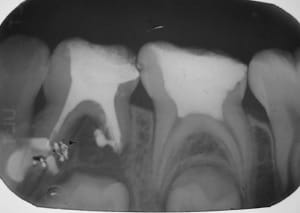

Mi hijo desde que le salieron los primeros dientes ha tenido problemas en ellos (caries, molestias).. Según los médicos por la cefalexina, ampicilina y otros que me suministraban en el embarazo y luego a el cuando nació amoxicilina.. Ha sido un martirio desde muy pequeño en el odontólogo... :'( pero lo que me preocupa comenzó hace poco mas de un año, me dijeron que tenia una caries grande en una muelita y que le debían hacer endodoncia o algo así, la cosa fue que le abrieron un hueco a la muela y le metieron un algodón con medicamento y se lo dejaron ahí como 2 meses mas o menos y el niño se quejaba constantemente pero la odontóloga decía que era normal pero le salio una bola grande en el colmillo del lado de la muela tratada la cual estaba llena de pus... Igual me seguían diciendo que no era nada grave y en la muela en esos dos meses no le hicieron revisión ni nada...

Luego este año en los primeros días de enero le volvieron a realizar lo mismo (hueco, algodón, medicamento) y lo volvieron a cerrar.. En este caso también sentía molestia y lloraba mucho, le volvió a salir la bola en el colmillo del lado pero ahora mas grande y a parte también le salio otra en la muela de atrás (la que sigue a la tratada).. Va para 4 meses con este algodón ahí dentro